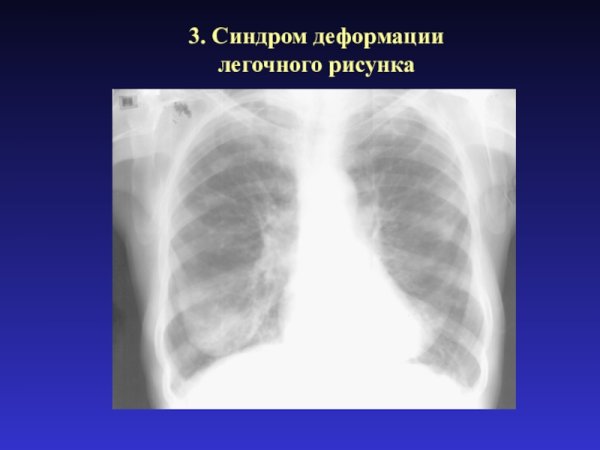

Синдром деформации легочного рисунка

Деформированный легочный рисунок - это состояние, при котором наблюдается изменение обычного внешнего облика легких на рентгенограмме. Такое отклонение может быть связано с различными заболеваниями и патологическими процессами, такими как хронические обструктивные заболевания легких, фиброз, опухоли или воспалительные процессы. Деформированный легочный рисунок может представлять собой уменьшение объема легочной ткани, нарушение архитектуры легочных сосудов или изменение контуров легочных полей. Раннее выявление и диагностика таких изменений могут помочь в раннем начале лечения и улучшении прогноза для пациента.